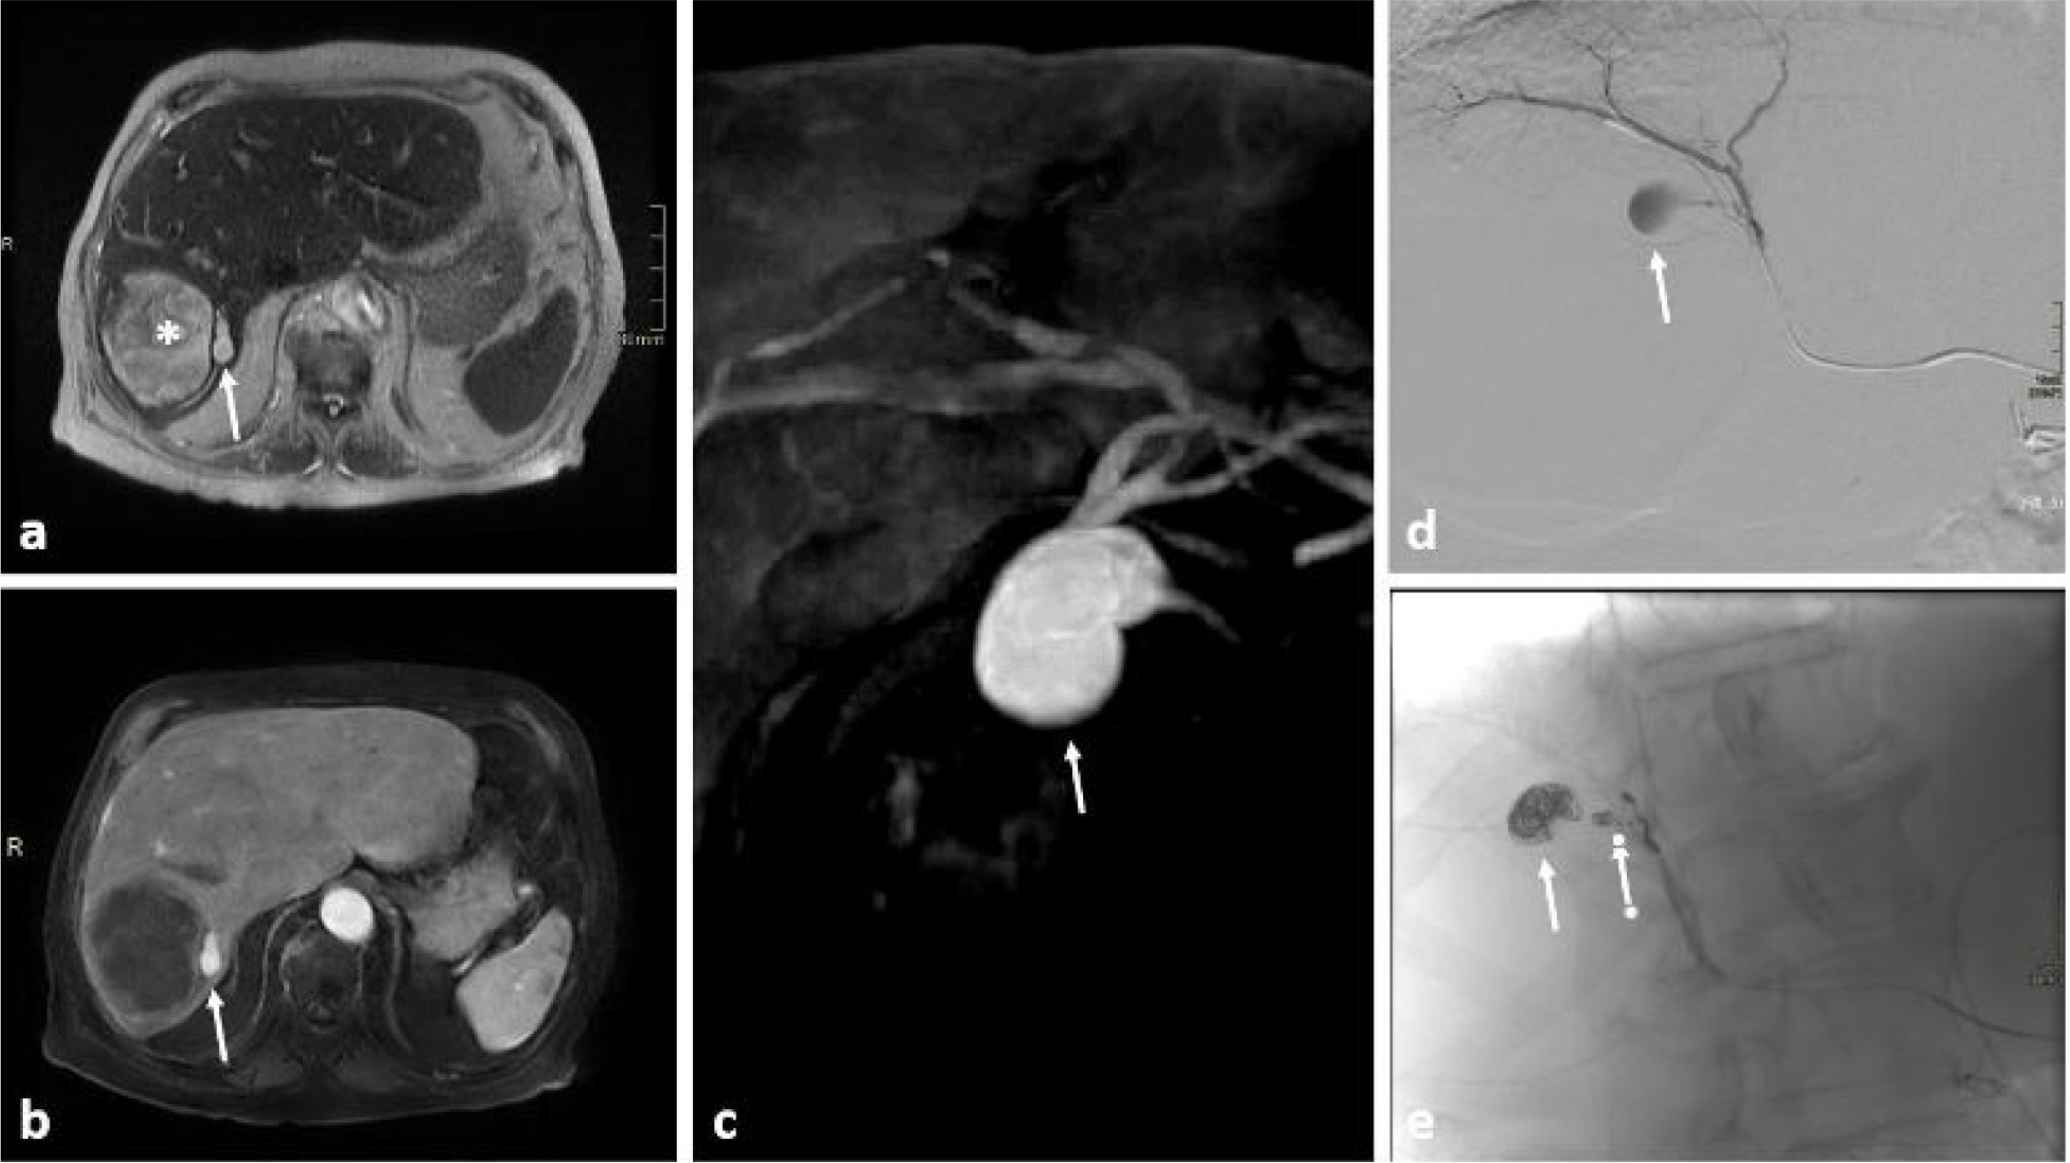

A follow-up abdominal MRI was performed a month later showing a slight decrease in the size of the previously seen liver hematoma. In addition, a small (10 mm) focal aneurysmal vascular dilatation was noted adjacent to the mass. These findings suggested that the hematoma could be the result of a ruptured aneurysm. The patient underwent a successful embolization by coiling of the intraparenchymal hepatic artery aneurysm (Figure 1). His hemoglobin progressively improved and was stable at 10.5 g/dL after 3 months.

Abdominal MRI sequences (a–c) and arterial hepatic angiography (d and e). Axial T2 image of the midportion of the liver (a) showing a large heterogenous formation between segment VI and VII (asterisk) with an adjacent small ovoid formation of intermediate signal (arrow). The large formation is not enhancing in axial T1 image post contrast injection (b) while the ovoid formation is vividly enhancing on the arterial phase (arrows in b and c) denoting its very probable aneurysmal origin (c: oblique maximal intensity projection reformatting of T1 sequence post contrast administration in the arterial phase). Selective hepatic catheterization and angiography confirming the presence of the aneurysm (arrow in d) that was successfully embolized with its branch by multiple coils (arrows in e).